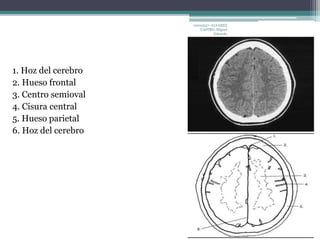

1. Hoz del cerebro

2. Hueso frontal

3. Centro semioval

4. Cisura central

5. Hueso parietal

6. Hoz del cerebro